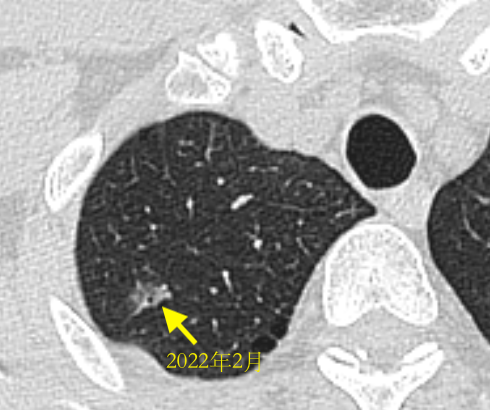

1年半前发现时的结节,直径1.2厘米

这位患者的CT影像是比较典型的早期肺癌影像,当地医生建议早做手术是对的,医生一般会重点关注以下几个结节特征:

1、大小 :这个结节最大直径1.2厘米

2、密度: 其内可见部分实性密度,属于混合密度结节,已经有了浸润的可能;

3、外部形态:可见边缘不整,毛刺征,胸膜牵拉征

4、内部结构:内部可见空泡征

5、血管集束征:该患者增强CT可见结节内血管集束征,且血管形态似有扭曲、牵拉